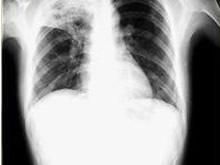

2.X線檢查

X線攝片檢查,肺紋理增厚、模糊為腺病毒肺炎的早期表現。肺部實變多在發病第3~5天開始出現,可有大小不等的片狀病灶或融合性病灶,以兩肺下野及右上肺多見。發病後6~11天,其病灶密度隨病情發展而增高,病變也增多,分布較廣,互相融合。病變吸收大多數在第8~14天以後。肺氣腫頗為多見,為雙側瀰漫性肺氣腫,可有胸膜改變,多在極期出現胸膜反應,或有積液。